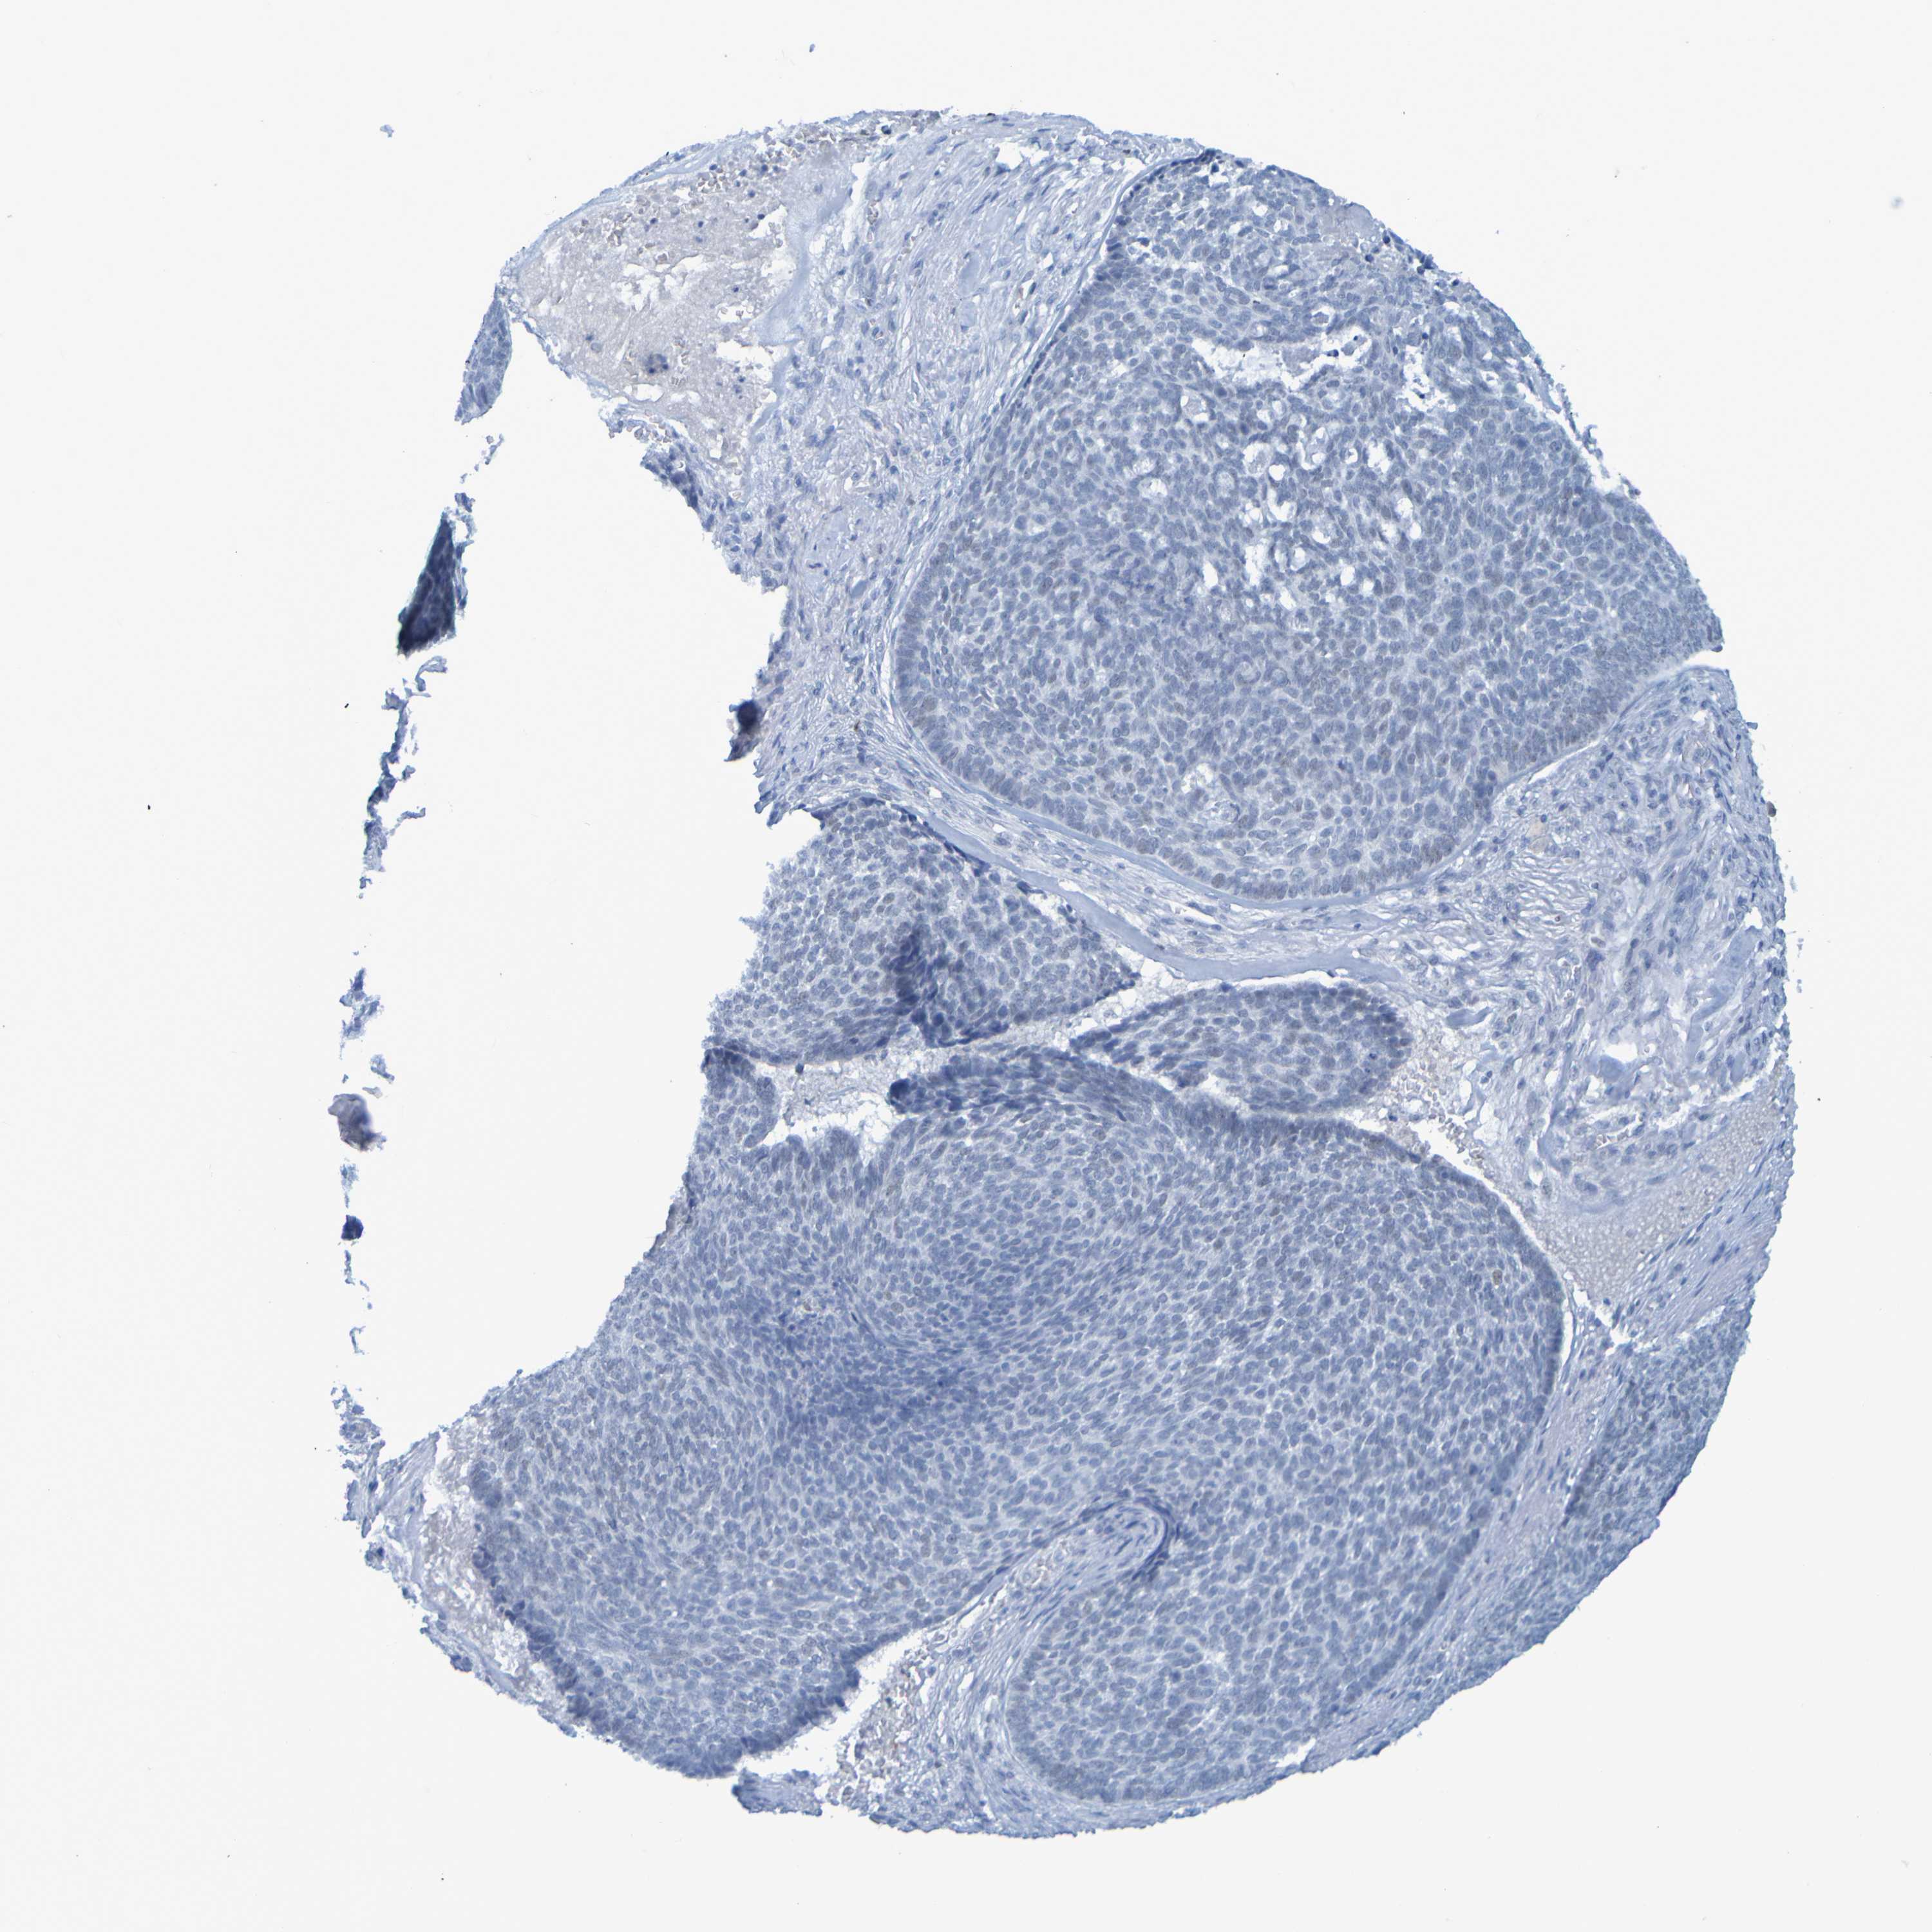

SKIN CANCER - Protein expressioni

A mouse-over function shows sample information and annotation data. Click on an image to view it in a full screen mode. Samples can be filtered based on level of antibody staining by selecting one or several of the following categories: high, medium, low and not detected. The assay and annotation is described here.

Each image is clickable and will lead to virtual microscopy that enables deeper exploration of all samples and also displays staining intensity scores, fraction scores and subcellular localization as well as patient and tissue information for each sample.

Antibody HPA012082

Staining

High

Intensity

Strong

Quantity

>75%

Location

Nuclear

Squamous cell carcinoma, NOS

Basal cell carcinoma

Adnexal tumor, benign